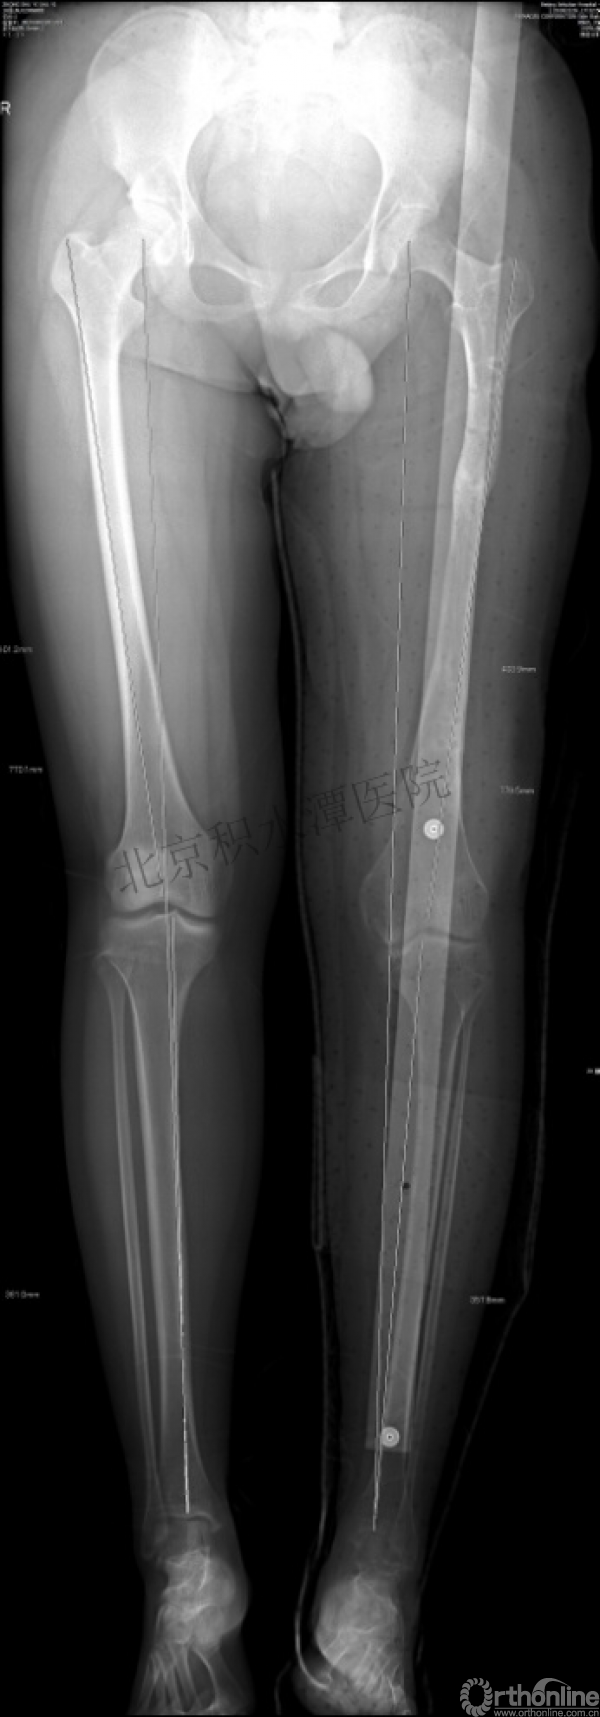

男孩、9岁,滑雪受伤,胫腓骨螺旋形骨折(粉碎性)

这个病例郭教授在积水潭医院骨科高研班时多次讲到,也在互动交流中惊人地看到,了解到现实之令人难以想象!

手法整复,石膏制动!

整复后7天

儿童具备强大的愈合潜力,同样也有极强的塑形能力

某种情况下,The best treatment is no treatment! 最佳治疗反而是不治疗!因为很多骨折依靠儿童强大的塑形能力和特点完全可以得到满意的结果!